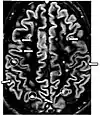

Fluid-attenuated inversion recoveryFLAIRFluid suppression by setting an inversion time that nulls fluidsHigh signal in lacunar infarction, multiple sclerosis (MS) plaques, subarachnoid haemorrhage and meningitis (pictured).[57]

Double inversion recoveryDIRSimultaneous suppression of cerebrospinal fluid and white matter by two inversion times.[58] High signal of multiple sclerosis plaques (pictured).[58]